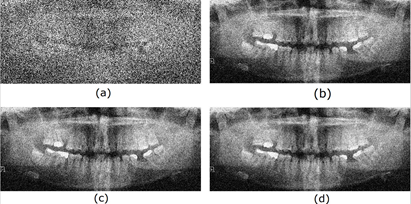

Finally, the radiological images restored using different adaptive filters are presented. Figures 6, 7, 8, and 9 show the noisy and restored images using different 2D adaptive filtering algorithms, respectively. From visual observation, it can be seen that the proposed filter produces a smoother version of the image and, thus, a slightly higher noise reduction compared to the LMS and 2D-NLMS algorithms. Furthermore, the proposed filter improves the visualization of the elements present in the image by more accurately highlighting transitions or edges. This enhancement means that details and structures of interest in the image become more discernible and can be appreciated with greater clarity.

Figure 3 shows the radiological images used for the simulation. These images are available in an open-source database [9]. The access path to the images is as follows: DentalPanoramicXrays.zip → Images → 1.png, 29.png, 58.png, 116.png.